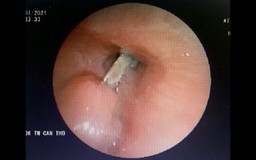

Bình Phước: Gắp ra xương cá dài 4 cm đâm sâu trong dạ dày bệnh nhân

Gắp ra xương cá dài 2,5 cm gây thủng ruột non bệnh nhân